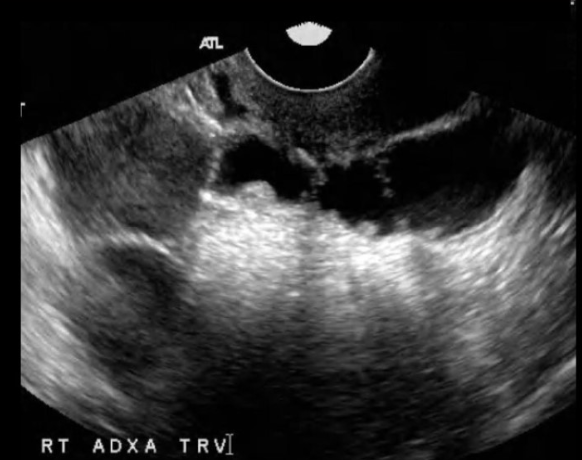

a 27 yo complains of pelvic fullness

a) ovarian hyperstimulation syndrome

b) ovarian lymphoma

c) bilateral endometriomas

d) Krukenberg tumor